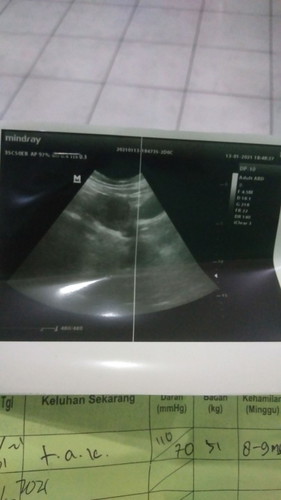

pertama usg itu tgl 13 januari2021 hasil nya baru penebalan rahim dan kantong pun blm kelihatan , selang 2 minggu tepat 27 januari kmrin usg lagi alhamdulilah sudah ada kantong tapi janin blm terlihat ,, mungkin saya jga lupa terakhir haid kapan karna keinget terus janin yg pertama keguguran , seinget saya terakhir haid itu 14 nov 2020 dan sampe skrg blm haid jga nah iseng lah alhamdulilah tespeck dan positive garis 2 ,, dan kmrn hasil usg kedua karna tidak sesuai dengan uk klo 2 minggu ga ada perubahan berkembang nya janin harus di kuret kali kedua ,,, pas dokter bilang gtu rasanya hancur sejadi" nya bingung mau kaya gmn rasa nya harus gagal lagi menjadi perempuan seutuh nya ,, uk janin 6w6d waktu usg kedua apa ganti dokter aja ? #bantusharing